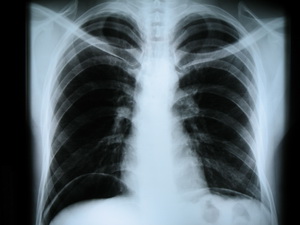

Рентген или манту детям: равно опасный выборВ связи с вступлением в силу в силу новых санитарно-эпидемиологических правил СП 3.1.2.3114-13 "Профилактика туберкулеза" непривитых детей начали более активно направлять к фтизиатрам. Фтизиатры обычно предлагают родителям сделать ребенку либо Манту (Диаскин) либо рентген. Однако не все родители знают, что в России рентген детям в большинстве случаев запрещен, а в пробе Манту и Диаскин-тесте есть опасные вещества.

Рутинным рентгеновским исследованиям грудной клетки не может быть места при решении каких бы то ни было вопросов в педиатрии. Рутинные рентгенограммы грудной клетки не должны выполняться просто потому, что ребенок нездоров. До того как делать больному снимки, необходимо убедиться в наличии явных клинических проявлений. !!! Эксперты ВОЗ считают безосновательным проведение рутинной рентгенографии при поступлении больного в стационар без должных показаний к обследованию грудной клетки, то же относится к предоперационной подготовке, если у больного нет клинических проявлений заболевания органов грудной клетки.

К сожалению, похоже, фтизиатры также не знают о том, что рентген нельзя использовать для диагностики туберкулеза без клинических проявлений. И в этой статье я расскажу об опасности рентгена подробнее.